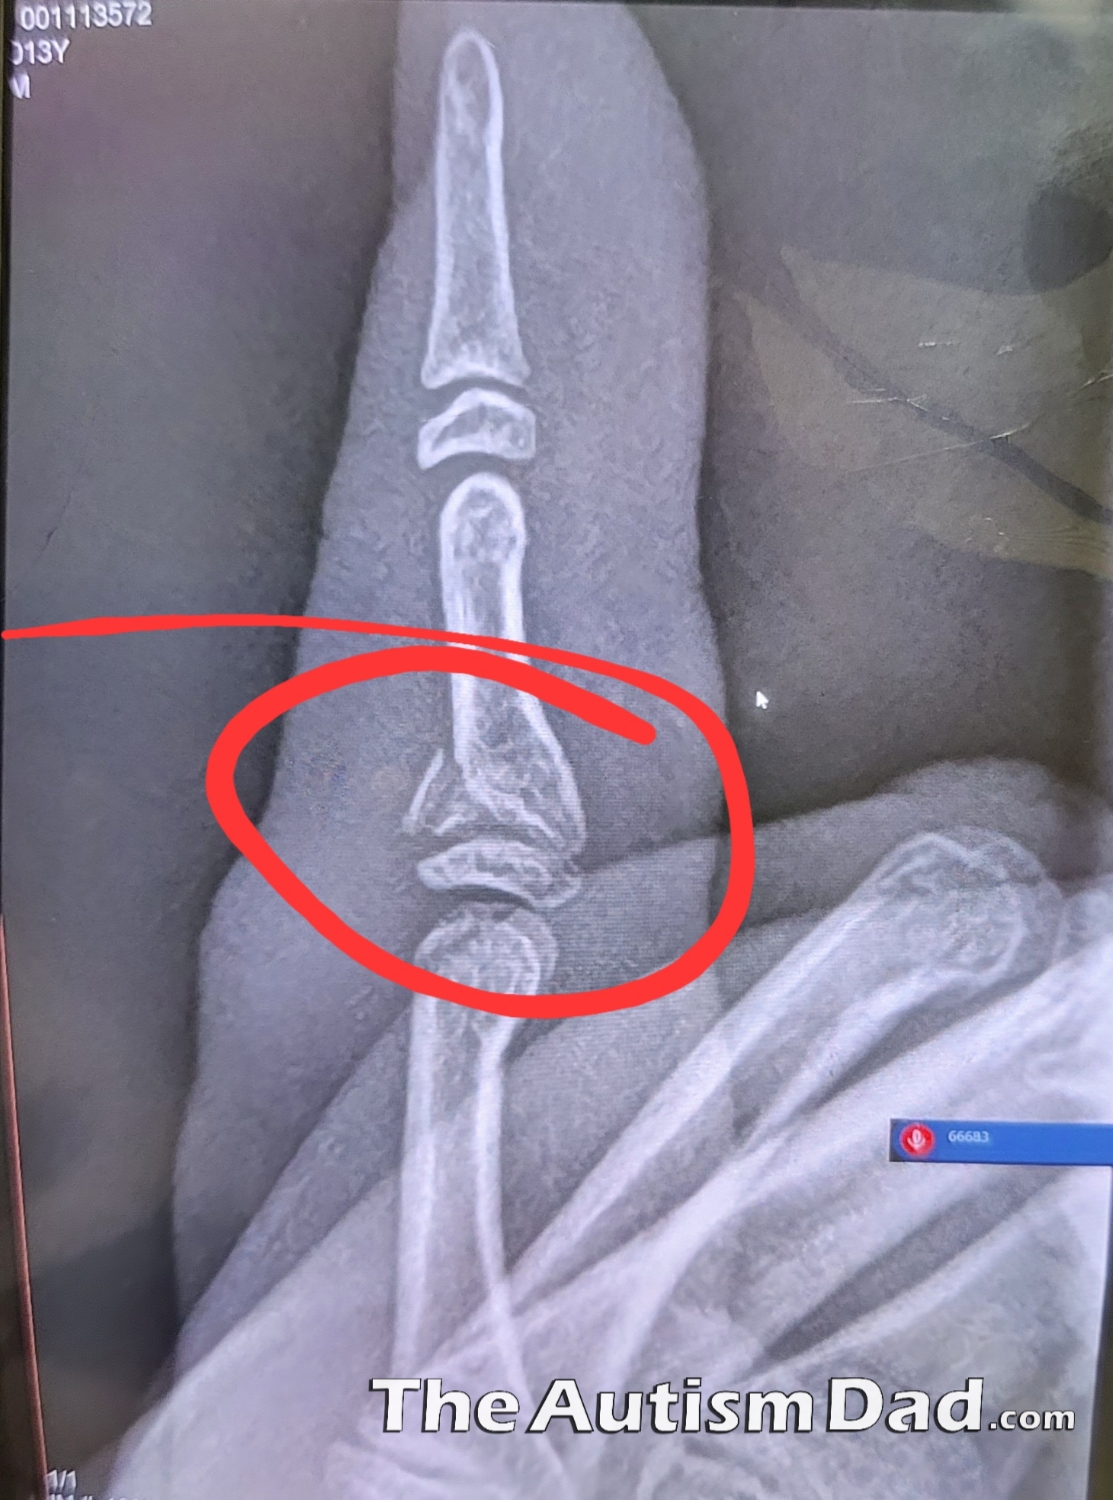

I realized that I forgot to mention that Emmett broke his finger on Friday. It happened at school during recess and by the end of the day, it was pretty obvious that it was more than just a minor injury. A quick trip to my parents house to see what they thought and we were off to urgent care.

He has to wear a splint for the next month or so and I need to get him a follow-up in orthopedics. The original referral was to a local hospital tied to te urgent care, but I'm going to switch him back over to Akron Children’s Hospital for this follow-up. It should heal just fine but he needs new xrays in a week or so to make sure.

There's a bit of struggle with the splint as it's not super comfortable and for a kid like Emmett, it's very distracting and not sensory friendly. He's doing quite well with it and wears it for 95% of the day though. I think he's okay and I'm going to get him into Akron Children's next week, hopefully.